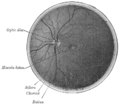

الجزء الداخلي من النصف الخلفي من مقلة العين اليسرى. الأوردة أغمق في المظهر من الشرايين. (الشريان المركزي للشبكية مرئي ولكن بدون تسمية).